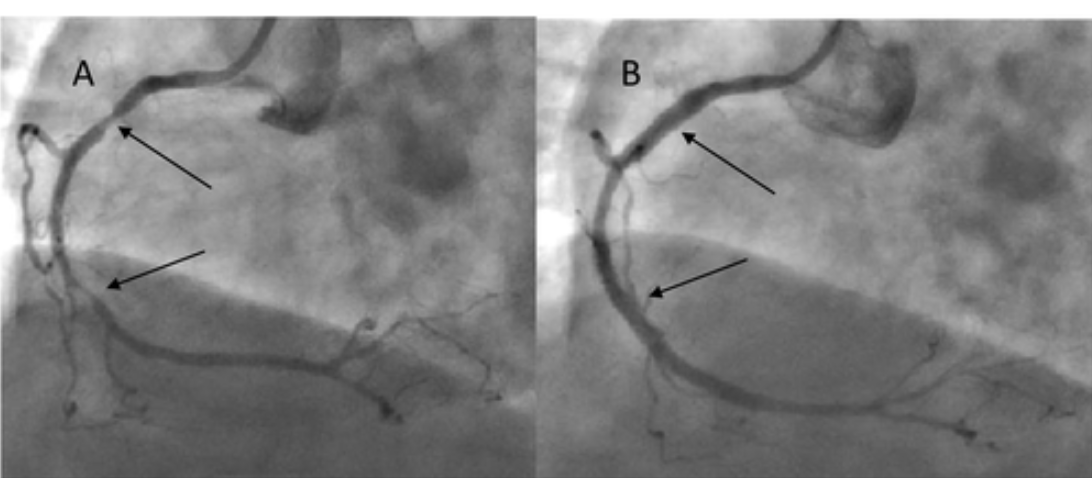

干预前两天,停用二甲双胍治疗,而雷米普利剂量减半至2.5mg。用40 mL低渗碘对比剂(碘普罗胺)进行冠状动脉造影,发现有两支冠状动脉病变。在左前降支(LAD)内侧段检测到 90%-99%的钙化狭窄,在远端段检测到90%狭窄,在第一对角支中检测到90%-99%狭窄。在右冠状动脉 (RCA) 中观察到两个主要狭窄:近端段为 70%-90%,内侧段为90%-99%。患者不同意手术血运重建,因此计划进行经皮冠状动脉介入治疗 (PCI)。四天后,在适当补液后进行 PCI,在 LAD 中植入两个药物洗脱支架,并对第一对角分支进行球囊血管成形术(图 1)。此外,三个裸金属支架植入 RCA(图 2)。考虑到手术的复杂性,使用了225 mL低渗碘对比剂,然后充分补液。然而,尽管采取了这些预防措施,干预后 36小时肾功能恶化,血尿素氮(15.7mmol/L)和血清肌酐(从150-227μmol/L)升高,但仍持续利尿。

图2